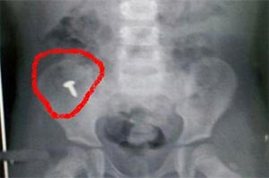

وتقول الأم "انتظرت ولم أجد تغييراً على الطفلة، وكان الوقت متأخراً، وفي صبيحة اليوم التالي توجهت بها للمستشفى، وبعد عمل الأشعة تأكد وجود المسمار، إلا أن الدكتور قال لنا إن المسمار نزل أسفل البطن في القولون، ومن الصعب إخراجه الآن، لأنه نزل من المعدة، ولو كان في المعدة لعملنا لها منظاراً وأخرجناه، وقال الدكتور ليس أمامنا الآن إلا الانتظار لمدة ثلاثة أيام، وإن استقر مكانه فربما نتدخل جراحياً لإزالته".